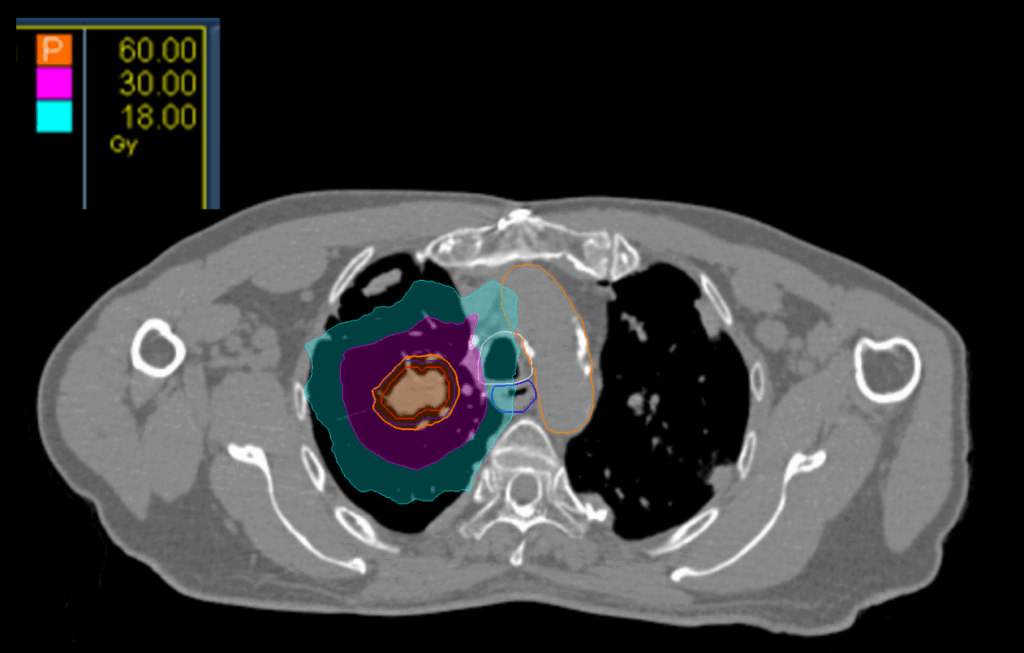

Treatment Plan Images

Treatment Planning Highlights

Fractionation

60 Gy in 8 fractions

PTV(s) Volume

21.8cc

Dose Distributions

- Prescription to the

78.9% isodose line - Max. dose 76.05 Gy

New Conformality Index (nCI)

nCi = 1.22

Gradient Index (GI)

GI = 4.24